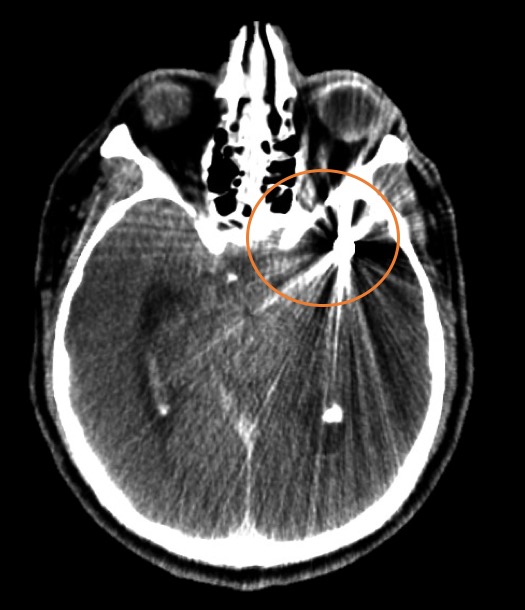

Fig. 1. TC de cerebro sin contraste: corte axial, evidenica HSA Fisher IV, Mayor espesor de HSA con hematoma asociado a nivel del valle Silviano izquierdo (circulo naranja). Volcado hemático ventricular en astas posteriores de ventrículos laterales (ver flecha).

La edad de presentación y distribución del genero de los casos estuvo dentro del rango descripto en la literatura. La identificación del sitio correcto del aneurisma responsable del sangrado es posible en muchos casos, basada en la presencia de algunos signos presentes en la TC de cerebro simple inicial [51]. Siendo el signo más confiable, el espesor de un Coágulo >3mm localizado en el espacio subaracnoideo. También en algunas ocasiones se puede encontrar un centro hiperdenso dentro de la región de mayor cantidad de HSA, el cual representaría la localización del aneurisma responsable de la hemorragia. Otro signo importante, es el patrón de distribución de la hemorragia: por ejemplo, una gran cantidad de sangre dentro de la cisura interhemisférica y la cisterna supraselar comúnmente indica una ruptura de un aneurisma comunicante anterior (ACOMA) o del segmento A1 o A2 de la arteria cerebral anterior; Mientras que la sangre principalmente confinada a la cisura de Silvio se asocia con aneurismas de la bifurcación de la arteria cerebral media (ACM); Los sangrados a lo largo de las cisternas basales pueden señalar característicamente la ruptura de los aneurismas del TIP o del tronco basilar, así como también estos mismos sangrados con prevalencia hacia la derecha o izquierda con hemorragia intraventricular, pueden ser característicos de ruptura de aneurismas de la arteria cerebelosa posteroinferior (PICA).

Otra forma de analizar la distribución de la HSA en relación a la ubicación del aneurisma roto, se realizó verificando si había una capa vertical de sangre subaracnoidea de más de 3 mm de espesor o un coágulo de sangre localizado en topografía de cada uno de las siguientes localizaciones, ACI: arteria carótida interna, TIP ACI: bifurcación carotidea, ACM: arteria cerebral media, ACA: Arteria cerebral anterior, ACOMA: arteria comunicante anterior, Vertebro/PICA: segmento V4 de la arteria vertebral, BA: tronco de la arteria basilar, TIP BA: bifurcación de la arteria basilar, ACP: Arteria cerebral posterior.